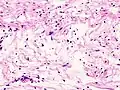

| Micrograph of a schwannoma showing both a cellular Antoni A area (top) and a loose paucicellular Antoni B area (bottom). HE stain. | |